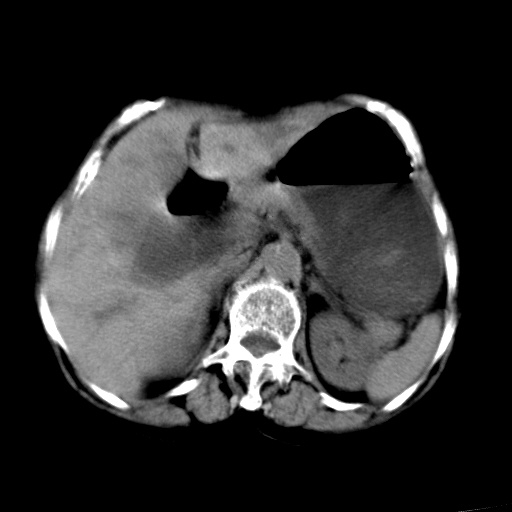

以下是引用杀毒软件在2009-3-4 17:38:00的发言:[br]为何没有喝照影剂呀? 胆总管及肝内胆管扩张,增强吧。[br][br]考虑-----十二指肠占位----建议----十二指肠镜检查[br][br]

以下是引用jiangjing在2009-3-4 17:45:00的发言:[br]低位胆道梗阻。十二指肠降段局部管壁增厚。扫描效果不理想,建议ct增强及ercp。

以下是引用杀毒软件在2009-3-4 17:38:00的发言:[br]为何没有喝照影剂呀? 胆总管及肝内胆管扩张,。增强吧。[br][br]考虑-----十二指肠占位----建议----十二指肠镜检查[br][br][br][br][本贴已被 杀毒软件 于 2009-3-4 17:56:38 修改过]